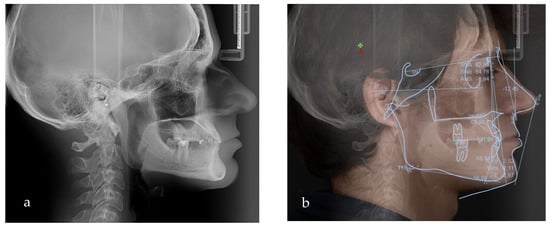

Figure 5.

(a) Lateral teleradiograph; (b) VTO analysis.

Based on the clinical and paraclinical examination, the following diagnostics were established: skeletal and dental class III anomaly (ANB angle −1°), with hypodivergent growth pattern and anterior rotation of the mandible (Sn-GoGn 28°), maxillary hypoplasia, slightly protruded upper incisors, diastema, spacing due to anodontia of the lower central incisors, all lateral incisors, all canines, all premolars and three second molars. Therefore, in this clinical case, seven permanent teeth were present.

To evaluate the treatment options and the amount of posterior rotation of the jaws required to improve the facial appearance, the VTO (Romexis) was formed (Figure 5b).

Based on the VTO (visualized treatment objective), protraction and posterior rotation of the maxilla would have been the ideal treatment option in terms of skeletal modifications; however, this treatment option would have needed an orthognathic surgical approach (which was not accepted by the patient).